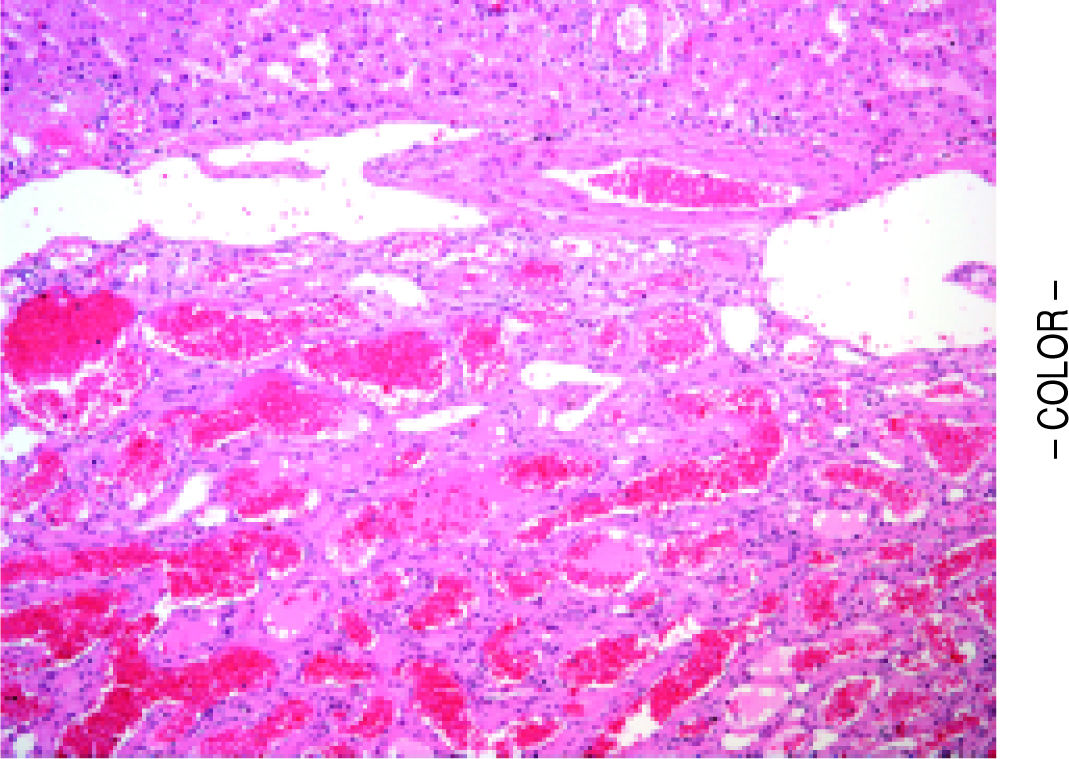

Hepatic Cavernous Hemangioma, Light Micrograph Stock Photo